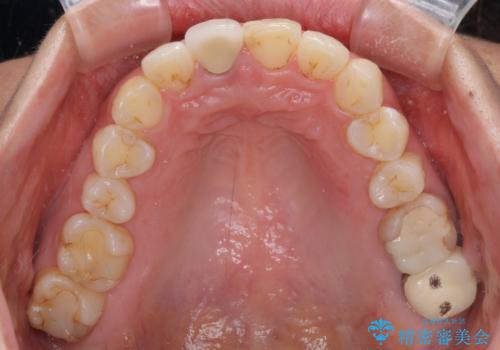

目立つ前歯の詰め物 オーダーメイドのセラミッククラウンで審美的に仕上げる

- 前歯のプラスチックが変色していることを気にして来院された患者様です。

反対側同名歯にセラミッククラウンが装着されていたため、そちらのクラウンと形態や色彩を揃えるようオーダーメイドタイプのオールセラミッククラウンにて補綴することとしました。

2本同時に処置をし、2本とも明るい色合いにすることをお勧めしましたが、今回は1歯のみとしました。

左右のバランスが取れ、患者様には大変満足していただきました。